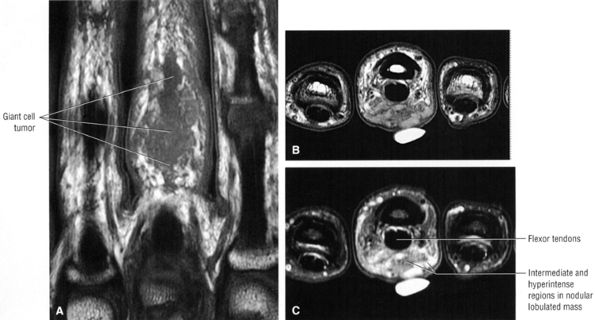

Associated dorsal ganglions in the dorsal or dorsal/membranous scapholunate ligament pathology (Fig. 10.100).